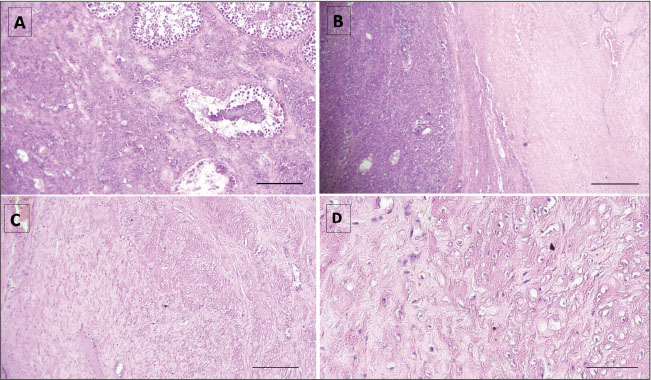

Fig. 2. Histological sections of seminoma in the testis of an Arabian-Barbe stallion. A: Overview of seminoma showing the general lobular architecture of the tumor (H&E, ×10; bar=160 µm). B: Presence of fibrous trabeculae (white arrows) separating tumor lobules, illustrating the structural organization within the seminoma (H&E, ×10). C: Nuclear atypia within tumor cells, including karyorrhectic nuclei (arrowhead) and anisokaryosis (asterisk), indicating cellular pleomorphism and active tumor proliferation (H&E, ×40; bar=90 µm). D: Mitotic figure (black arrow) highlighting active cell division, a feature of tumor growth and malignancy (H&E, ×40; bar=90 µm). The nodular lesion was well-circumscribed and, on cut section, displayed a whitish, fasciculated appearance without evidence of gross necrosis. Histological evaluation of H&E-stained sections revealed a benign mesenchymal neoplasm composed of interlacing fascicles of spindle-shaped cells. The neoplastic cells exhibited elongated, uniform nuclei with finely dispersed chromatin and moderately eosinophilic cytoplasm, consistent with smooth muscle differentiation (Fig. 3C, D). The fascicular architecture was prominent, and the tumor stroma contained scattered thick-walled blood vessels. Mitotic activity was low, with two to three mitotic figures per ten high-power fields. No areas of tumor necrosis, cellular atypia, or other features suggestive of malignancy were observed, supporting the diagnosis of leiomyoma.

Fig. 3. Histological features of seminoma and leiomyoma within the same testis in an Arabian-Barbe stallion. A–B: Interface between seminiferous tubules and the leiomyoma, showing distinct tissue separation (H&E, ×10; A: bar=200 µm, B: bar=340 µm). C: Well-circumscribed leiomyoma composed of spindle-shaped smooth muscle cells with elongated, regular nuclei and no signs of malignancy (H&E, ×10; bar=340 µm). D: Higher magnification of smooth muscle tumor cells, highlighting uniform nuclei and fascicular architecture (H&E, ×40; bar=160 µm). Both neoplastic components were located within the same testis. The seminoma occupied the central parenchyma, while the leiomyoma formed a well-circumscribed, septate proliferation. The two lesions were adjacent but remained distinctly separated, with no intermingling of cell populations (Fig. 3A, B). Ethical approvalEthical approval was not required, as this work reports a single clinical case managed within normal veterinary practice. DiscussionAlthough equine testicular tumors are considered uncommon and their true prevalence remains unclear (Leidinger et al., 2018), available data are largely derived from individual case reports, partly because most horses are castrated at a young age, limiting long-term monitoring of intact stallions (Schumacher, 1999; Valentine, 2009; Peeters et al., 2024). Among equine testicular neoplasms, seminoma is the most frequently reported tumor type (Brinsko, 1998; Valentine, 2009). Seminomas arise from spermatogenic cells and are typically unilateral, with a reported predilection for the right testis, although bilateral involvement has been described (MacLachlan and Kennedy, 2002; Scott et al., 2015). Advanced seminomas may become diffuse and replace most of the testicular parenchyma (Farjanikish et al., 2016; Leidinger et al., 2018). In the present case, the tumor involved the right testis, occupying approximately two-thirds of the parenchyma, with a small additional neoplastic lesion identified in the contralateral testis. Histopathological examination revealed the coexistence of a seminoma and a leiomyoma within the same testis, with seminoma representing the predominant component. Furthermore, equine seminomas are reported to grow relatively rapidly and may exhibit a higher metastatic potential than in other domestic species (Brinsko, 1998; Agnew and MacLachlan, 2016; Meuten, 2020). Palpation of the affected testis is often non-painful, which may contribute to delayed recognition and postponement of surgical intervention. As a result, clinical signs are frequently vague or intermittent, including mild discomfort, occasional colic-like episodes, or pain during ejaculation, and may therefore go unnoticed for prolonged periods (Christensen et al., 2007). In horses, although malignant presentations of seminoma are considered less frequent, this tumor appears to behave more aggressively than in other species, with metastatic spread reported primarily to abdominal and regional structures (Brinsko, 1998; Beck et al., 2001; Valentine, 2009; Knottenbelt et al., 2015; Agnew and MacLachlan, 2016; Meuten, 2020). Delayed diagnosis and treatment may therefore allow progressive tumor growth and increase the risk of metastatic disease, which has been associated with poor prognosis. When metastasis occurs, reported survival time ranges between 10 and 24 months (Christensen et al., 2007). This aggressive behavior has been illustrated in a case of intra-abdominal seminoma arising from a cryptorchid testis, in which extensive metastatic disease was identified at necropsy 18 months after surgery (Peeters et al., 2024). In the present case, castration was postponed until progressive tumor enlargement resulted in visible discomfort and aesthetic concerns during public appearances. This delay, influenced by the cultural context in which stallions are traditionally maintained intact, highlights a potential conflict between cultural practices and animal welfare considerations. Prolonged maintenance of an affected testis may expose the animal to chronic discomfort and increase the risk of advanced or metastatic disease, emphasizing the importance of timely clinical evaluation and intervention. These findings underscore the need to prioritize animal welfare and clinical decision-making over aesthetic or cultural considerations in the management of intact stallions. In cases of seminoma without evidence of metastasis, bilateral orchiectomy remains the recommended treatment, as affected stallions should not be maintained for breeding purposes (Govaere et al., 2010; De Lange et al., 2015; Farjanikish et al., 2016). Early surgical management is therefore essential not only for diagnostic confirmation but also to reduce welfare compromise and improve clinical outcome. A similar association of testicular neoplasms has rarely been described in horses. Weiermayer and Richter (2009) reported a Barb stallion with two distinct testicular tumors, a seminoma and a leiomyoma, each in a different testis. In contrast, the current case demonstrated both neoplastic lesions occurring within the same testis, with seminoma predominating. Previously, Cooper and Valentine (2002) described four cases of equine testicular leiomyomas, though the precise site of origin within the testicular architecture was unclear. According to Sisson (1975), testicular leiomyomas or leiomyosarcomas may originate from various smooth muscle elements, including the septula testis, testicular blood vessels, or the peritubular contractile cells of the convoluted and straight seminiferous tubules. In the case reported by Weiermayer and Richter (2009), the origin of the leiomyoma was considered unlikely to be peritubular, because the epididymis was not involved, as it typically would be if that were the case. In our case, determining the exact origin of the leiomyoma was challenging due to the close proximity of the two tumor types. In addition to the neoplastic lesions, a well-circumscribed hemorrhagic mass was identified adjacent to the epididymal region. This lesion was consistent with an epididymal hematoma, a finding not previously reported in horses. Such hematomas are likely to arise from rupture of small epididymal vessels, either after blunt trauma or secondary to venous congestion caused by the adjacent tumor. Stallions used for Tbourida are subjected to repeated physical exertion and scrotal impact during performances, which may contribute to local vascular injury and subsequent hematoma formation. An epididymal hematoma next to a testicular mass can make interpretation difficult, as it may mimic tumor extension or metastatic spread on ultrasound or during gross examination. Traumatic injuries of the external genitalia are considered reproductive emergencies because prompt management is essential to preserve fertility. Most cases occur during breeding, typically from a kick by the mare, but they may also result from attempts to jump fences or from impalement injuries sustained at pasture (DeVries, 1993; Perkins and Frazer, 1994; Sprayberry and Lu, 2021). To the authors’ knowledge, epididymal hematoma has not previously been reported in horses, and only a few isolated cases have been documented in humans, confirming the rarity of this lesion. Less than 1% of trauma-related injuries involve the scrotum, most of which result from athletic activity (≈50%), motor vehicle accidents (9%–17%), or assault (1%–2%). Among these injuries, those affecting only the epididymis are particularly uncommon and generally occur in association with testicular lesions (Guichard et al., 2008). Reported cases of epididymal or extratesticular hematomas in humans are scarce and mainly associated with blunt trauma or perioperative vascular compromise (Bonardi et al., 2011; Qi-Huang et al., 2021; Anastasiadis et al., 2022). ConclusionThe coexistence of two distinct neoplastic processes within a single gonad highlights the complexity and variability of testicular pathology in equines, and, in the present case, this was further associated with a well-circumscribed epididymal hematoma. This case underscores the importance of thorough histopathological evaluation to ensure accurate diagnosis, as mixed tumors may otherwise be overlooked or misclassified. Furthermore, this report contributes to the broader understanding of equine testicular disease by providing valuable insights into the spectrum of testicular lesions that may be encountered in stallions. Although the prognostic and reproductive implications of such combined lesions cannot be fully established on the basis of a single case, their recognition remains relevant for clinical decision-making and reproductive management in intact stallions. Awareness of these rare presentations may help guide appropriate therapeutic interventions and emphasize the need for further research into the pathogenesis, biological behavior, and long-term outcomes of mixed testicular tumors in horses. FundingNo external funding was received for this work. Authors’ contributionsZineb El Brini: Conceptualization; Investigation; Clinical examination; Data curation; Writing – Original Draft. Charifa Drissi Touzani: Investigation – Histopathology; Review & Editing. Abderrahmane Al Bouzidi: Writing – Review & Editing (histological sections). Mohammed Piro: Investigation; Clinical examination; Writing – Review & Editing; Final Approval of the Manuscript. All authors have read and approved the final version of the manuscript. Conflict of interestThe authors have no conflict of interest to declare. Data availabilityAll data supporting the findings of this study are available within the manuscript. ReferencesAgnew, D.W. and MacLachlan, N.J. 2016. Tumors of the genital systems.In Tumors in Domestic Animals. Meuten, D.J Anastasiadis, K., Godosis, D., Kepertis, C., Mouravas, V., Lampropoulos, V., Demiri, C., Tsopozidi, M. and Spyridakis, I. 2022. Partial epididymal rupture and spermatic cord haematoma with an associated secondary testicular torsion due to blunt scrotal injury in a 12-year-old boy. Afr. J. Paediatric Surg. 19(3), 183–185; doi:10.4103/ajps.AJPS_29_21 Bancroft, J.D. and Gamble, M. 2008. Theory and Practice of Histological Techniques. Batista, L.A.S., Santos Júnior, D.A., Rodrigues, A.S., Menezes, A.A., Nascimento, M.J.R., Galiza, G.J.N., Dantas, A.F.M. and Frade, M.T.S. 2024. Morphological and immunohistochemical characteristics of diffuse seminoma in horses: a case report. Reprod. Domestic Anim. 59(8), e14706; doi:10.1111/rda.14706 Beck, C., Charles, J.A. and Maclean, A.A. 2001. Ultrasound appearance of an equine testicular seminoma. Vet. Radiol. & Ultrasound. Off. J. Am. Coll. Vet. Radiol. Int. Vet. Radiol. Assoc. 42(4), 355–357; doi:10.1111/j.1740-8261.2001.tb00954.x Bonardi, M., Dellabianca, C. and Alessi, S. 2011. Post-traumatic hematoma of the epididymis: case report. J. Ultrasound 14, 196–198; doi:10.1016/j.jus.2011.09.001 Brinsko, S.P. 1998. Neoplasia of the Male Reproductive Tract. Vet. Clin. North Am. Equine Pract. 14, 517–533; doi:10.1016/S0749-0739(17)30184-0 Christensen, B.W., Ernst, N.S., Powe, J.R., Pozor, M.A., Morton, A.J. and Reinhard, M.K. 2007. Theriogenology Question of the Month. J. Am. Vet. Med. Assoc. 231(4), 531–534; doi:10.2460/javma.231.4.531 Cooper, B.J. and Valentine, B.A. 2002. Tumors of muscle. 4th ed. In Tumors in domestic animals. Ed., Meuten, D.J. Ames, IA: Iowa State Press, pp: 319–363. De Lange, V., Chiers, K., Lefère, L., Cools, M., Ververs, C. and Govaere, J. 2015. Malignant seminoma in two unilaterally cryptorchid stallions. Reprod. Domestic. Animals. 50(3), 510–513; doi:10.1111/rda.12488 Devries, P.J. 1993. Diseases of the testes, penis, and related structures.In Equine Reproduction. McKinnon JL Voss. and Eds. Philadelphia, PA: Lea & Febiger, pp: 873–97. Farjanikish, G., Sayari, M., Raisi, A. and Shirian, S. 2016. Diffuse type testicular seminoma in a stallion. Comp. Clin. Pathol. 25, 1133–1136; doi:10.1007/s00580-016-2316-z Govaere, J., Ducatelle, R., Hoogewijs, M., De Schauwer, C. and De Kruif, A. 2010. Case of bilateral seminoma in a trotter stallion. Reprod. Domestic Animals 45(3), 537–539; doi:10.1111/j.1439-0531.2008.01212.x Guichard, G., El Ammari, J., Del Coro, C., Cellarier, D., Loock, P.Y., Chabannes, E., Bernardini, S., Bittard, H. and Kleinclauss, F. 2008. Accuracy of Ultrasonography in Diagnosis of Testicular Rupture After Blunt Scrotal Trauma. Urology 71, 52–56; doi:10.1016/j.urology.2007.09.014 Knottenbelt, D.C., Patterson-Kane, J.C. and Snalune, K.L. 2015. Clinical equine oncology. London, UK: Elsevier. Leidinger, E., Springler, G., Furman, E. and Wallner, A. 2018. What Is Your Diagnosis? Testicular tumor in a horse. Vet. Clin. Pathol. 47, 166–167; doi:10.1111/vcp.12577 MacLachlan, N.J. and Kennedy, P.C. 2002. Tumors of the genital systems. 4th ed. In Tumors in domestic animals. Ed., Meuten, D.J. Ames, IA: Iowa State Press, pp: 547–573. Meuten, D.J. 2020. Tumors in domestic animals, 5th ed. Hoboken, NJ: John Wiley & Sons. Muir, W.W., Hubbell, J.A.E., Skarda, R.T. and Bednarski, R.M. 2018. Handbook of Veterinary Anesthesia. Pasolini, M.P., Della Valle, G., Pagano, T.B., Miele, F., Paciello, O., Fatone, G. and Greco, M. 2016. Mature teratoma arising from an undescended testis in a horse: comparison between ultrasonographic and morphological features. Folia Morphologica (Warsz) 75(2), 211–215; doi:10.5603/FM.a2015.0088 Peeters, C.M.P., Sterk, T., Grinwis, G., Giglia, G. and Rijkenhuizen, A.B.M. 2024. Colic signs caused by an unilateral abdominal seminoma in a Friesian stallion. Equine. Vet. Educ. 36, e176–e184; doi:10.1111/eve.13956 Perkins, N.R. and Frazer, G.S. 1994. Reproductive Emergencies in the Stallion. Vet. Clinics. North. Amer. Equine. Pract. 10(3), 671–683. Qi-Huang, S., Danilenko, A., Watson, C. and Krumenacker, J. 2021. Isolated extratesticular hematoma from intraoperative positioning during lumbar spinal surgery. Radiol. Case Rep. 16, 3746–3750; doi:10.1016/j.radcr.2021.09.011 Schumacher, J. 1999. Testicular neoplasia of horses: an underreported condition. Equine Vet. J. 31, 270–272; doi:10.1111/j.2042-3306.1999.tb03815.x Sedrish, S.A. and Leonard, J.M. 2001. How to perform a primary closure castration using an inguinal incision. In: Proceedings of the American Association of Equine Practitioners (AAEP), American Association of Equine Practitioners, Lexington, KY, 2001, Vol. 47. pp 423–424. Scott, C.J., Christensen, B.W., Dechant, J.E., Espinosa, P. and LaDouceur, E.E.B. 2015. Theriogenology question of the month. Neoplasms of the penis and testis. J. Am. Vet. Med. Assoc. 247(10), 1105–1108; doi:10.2460/javma.247.10.1105 Sisson, S. 1975. Urogenital system. 5th ed. In Sisson and Grossman’s the anatomy of domestic animals. Ed., Getty, R. Philadelphia, PA: W.B. Saunders, pp: 567–578. Sprayberry, K.A. and Lu, K.G. 2021. Managing Reproduction Emergencies in the Field: part 1: Injuries in Stallions; Injury of the External Portion of the Reproductive Tract and Gestational Conditions in the Mare. Vet. Clin. North. Am. Equine. Pract. 37, 339–366; doi:10.1016/j.cveq.2021.04.007 Talley, G. 2017. The gunpowder games: traditional equestrianism as Moroccan invented heritage tourism. In Equestrian cultures in global and local contexts. Eds., Adelman, M. and Thompson, K. Cham, Switzerland: Springer International Publishing, pp: 219 -240. Trigo, F.J., Miller, R.A. and Torbeck, R.L. 1984. Metastatic equine seminoma: report of two cases. Vet. Pathol. 21, 259–260; doi:10.1177/030098588402100223 Turner, R.M. 2019. Declining testicular function in the aging stallion: management options and future therapies. Anim. Reprod. Sci. 207, 171–179; doi:10.1016/j.anireprosci.2019.06.009 UNESCO. 2021. Tbourida (Morocco) – Representative List of the Intangible Cultural Heritage of Humanity. Available at: https://ich.unesco.org/en/RL/tbourida-01483 (accessed 12 November 2025). Valentine, B.A. 2009. Equine testicular tumors. Equine Vet. J. 41(5), 490–496; doi:10.2746/095777309X419342 Varner, D.D., Gibb, Z. and Aitken, R.J. 2015. Stallion fertility: a focus on the spermatozoon. Equine Vet. J. 47(1), 16–24; doi:10.1111/evj.12308 Weiermayer, P. and Richter, B. 2009. Simultaneous presence of a seminoma and a leiomyoma in the testes of a horse. Equine. Vet. Educ. 21, 172–176; doi:10.2746/095777309X400306